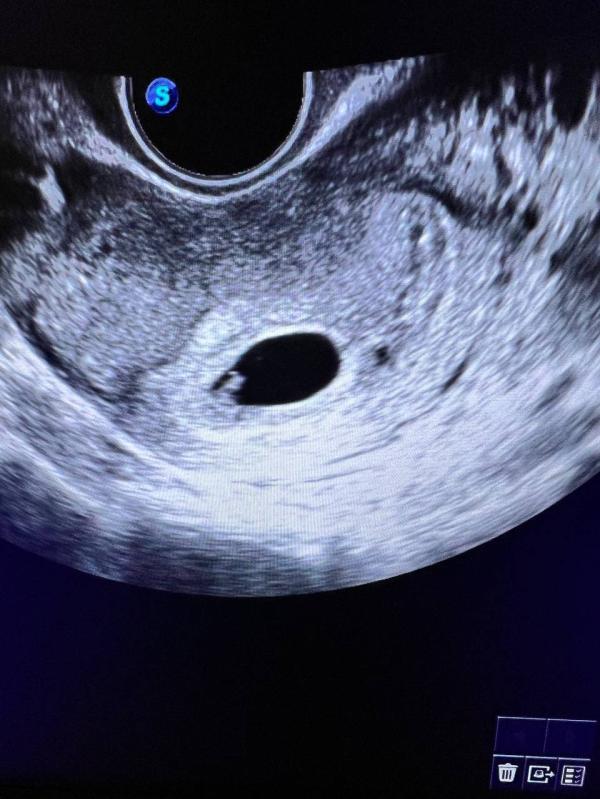

Сегодня ровно 6 акушерских недель.

Сходила на УЗИ, увидели эмбрион 2,2 мм и сердцебиение 148 уд.в мин., даже дали послушать 🥹